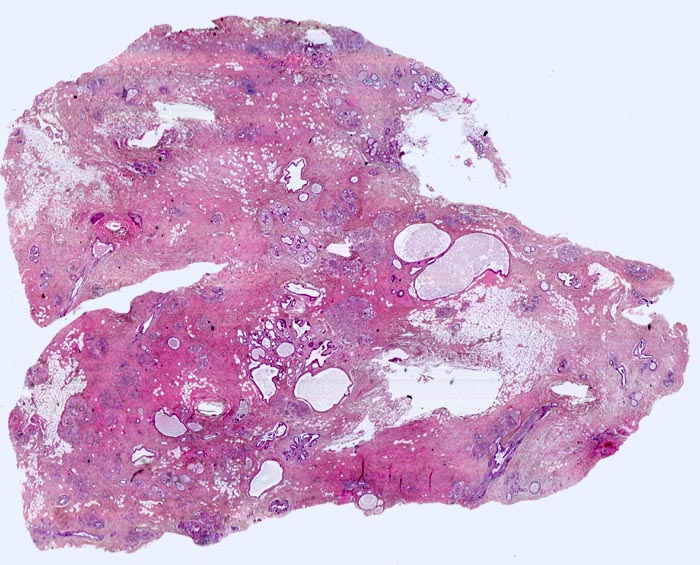

fibrös zystische Mastopathie mit Mikroverkalkungen

Ausgedehnte Fibroseareale schliessen kleine Inseln von Fettgewebe ein. Zahlreiche Gänge sind unterschiedlich stark dilatiert. Zusammen ergibt sich die Diagnose einer fibrös zystischen Mastopathie.

Probeexzision wegen umschriebenen Mikroverkalkungen in der Screeningmammographie. Bei der Palpation lassen sich mehrere unscharf begrenzte derbe Knoten tasten.

Histologie

Scan